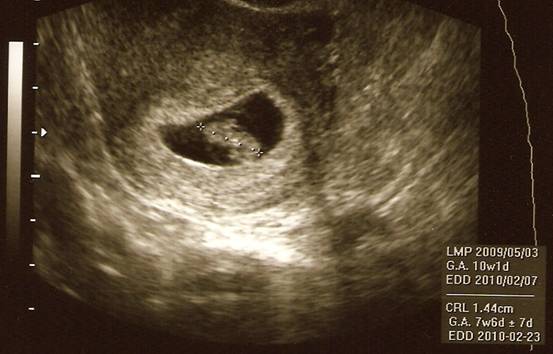

Ti biztos jobban tudjátok, a fehér pacnit kell nézni :)

Kép Chaos Engine (ahogy apa hívja) 7-8 hetes